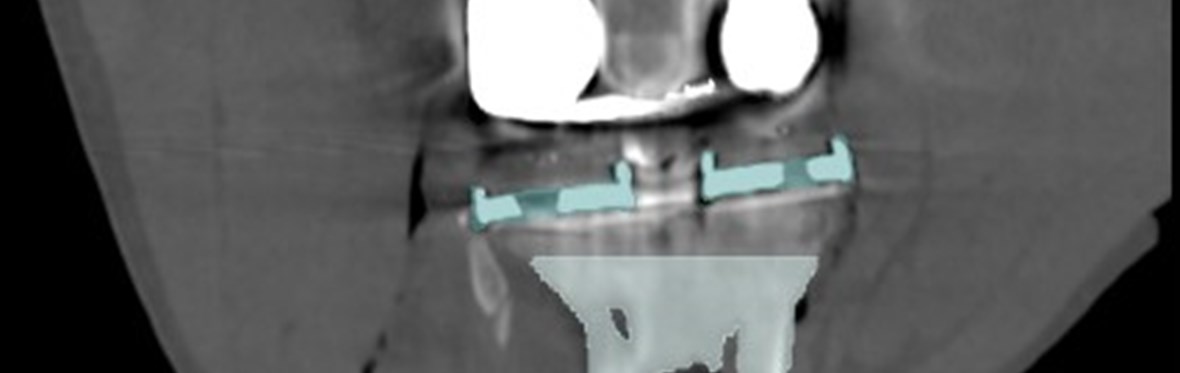

Adequate fixation of a revision (knee)implant is crucial for its survival. However, this is challenging due to bone loss and poorer quality of the remaining bone. By preoperatively examining the anatomy, reason for revision, and the amount and quality of bone before surgery, a tailored treatment can be developed to ensure proper fixation. The use of 3D CT-based migration analysis can help determine whether the fixation is adequate.